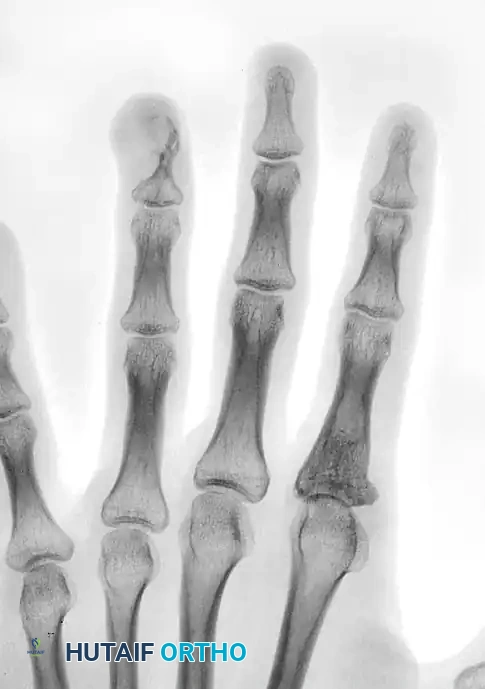

Image

FIGURE 77-11: Radiographic appearance of an osteoid osteoma. A small oval or round radiolucent nidus is surrounded by a dense halo of reactive sclerotic bone.

Lesions located in cortical bone or near the cortex may exhibit extreme, dense sclerosis that completely obscures the underlying nidus on standard plain radiographs. In such cases, fine-cut Computed Tomography (CT) is the imaging modality of choice to pinpoint the exact location of the nidus. A triphasic technetium-99m bone scan will also show intense focal uptake and can be helpful in confirming the diagnosis.